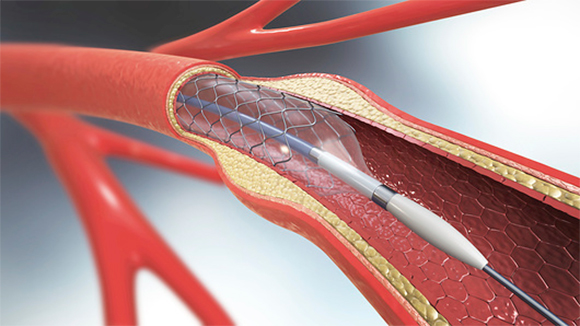

تُجرى قسطرة الوعاء الدّمويّ المسدود، وهو علاج أكثر توغّلًا في جسم المصاب، لتفتيت الانسداد أو لانتشاله. تزيد قسطرة الدّماغ الّتي تُجرى خلال ساعتين من اللّحظة الأولى لحدوث السّكتة كثيرًا من فرص التّعافي وسرعتها.

تزيد عمليّة إزالة الانسداد من الوعاء الدّمويّ خلال ساعتين من لحظة الإصابة بـ السّكتة الإقفاريّة من احتمال التّعافي منها. قسطرة شريان في الدّماغ | الرّسم التخطيطيّ: Christoph Burgstedt, Science Photo Library